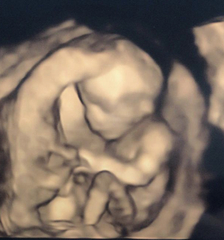

Nasal bone visible? Opinions appreciated!!

However whilst waiting for my cvs result I fell down a google rabbithole and am convinced now there’s something wrong with the babies nose. My midwife is brushing it off and I’ve an three week wait until my next scan. I had a private scan over the weekend but baby was facing away so they couldn’t get a clear profile. Attached are a couple of pics and the 4d scan is at 16 weeks. Can anyone tell me if they think I should worry / push to follow up further?

I'm not quite sure what you're worried about exactly when you say something is wrong. What could be wrong with the nose? I can see the nasal bone in the scan picture.

Ahhh thank you, that’s instantly made me feel better. I’d convinced myself no nasal bone is apparent! Dr google is the worst